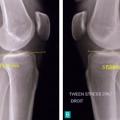

Rupture du ligament croisé antérieur

LESIONS PERI-ARTICULAIRES

LESIONS LIGAMENTAIRES

Image